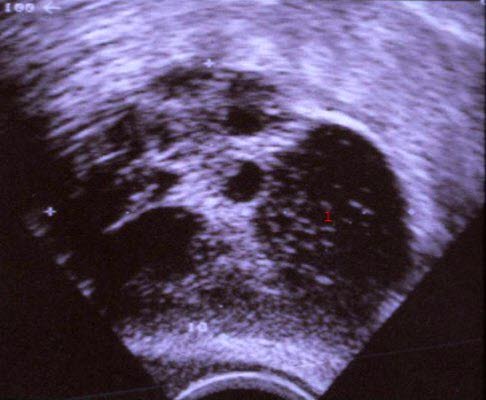

Ovariale teratomer

Godartede cystiske teratomer i eggstokkene oppdages som regel tilfeldig ved gynekologisk undersøkelse, i forbindelse med røntgenundersøkelser eller i forbindelse med magekirurgi av andre grunner. Symptomfrie ovariale teratomer er ikke så sjeldne. Symptomatiske teratomer kan gi magesmerter, oppfylning i buken eller unormale livmorblødninger. Blæresymptomer, magetarmplager og ryggsmerter er sjeldnere. Torsjon og akutt ruptur er vanligvis forbundet med sterke smerter.